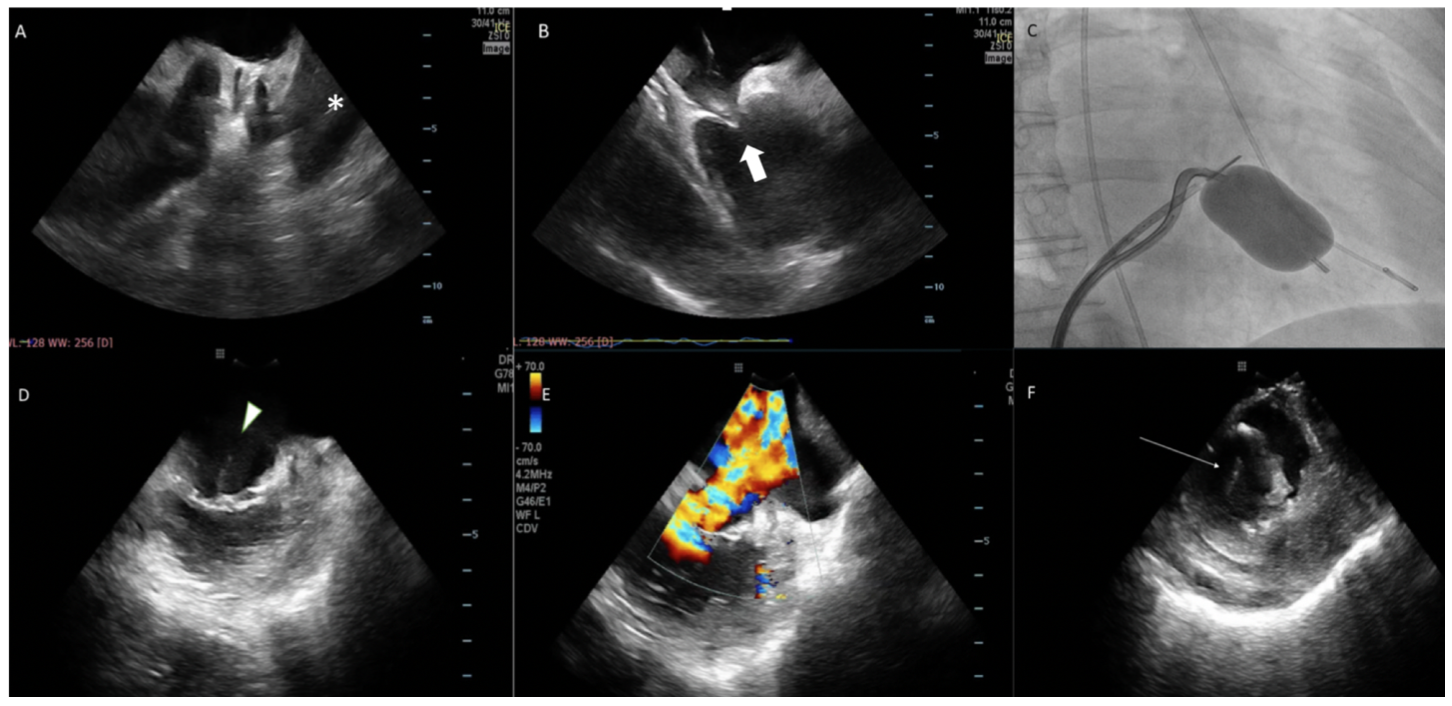

A 67-year-old woman was referred for PMC due to severe mitral stenosis. Pre-operative TEE showed favorable mitral anatomy. Under local anesthesia, ICE (ViewFlex Xtra; Abbott) was first positioned at the main pulmonary artery to exclude left atrial appendage (LAA) thrombus (Figure 1A). Transeptal puncture was guided by ICE at the right atrium (Figure 1B), aiming at inferior-posterior puncture to allow for more direct access to the mitral valve. An Inoue wire was then advanced into the left atrium under full heparinization. After dilatation of the interatrial septum with a 14 Fr dilator, the ICE catheter was advanced into the left atrium through the same transseptal site. The Inoue balloon was directed across the mitral valve and inflated to 24 mm under ICE and fluoroscopic guidance (Figure 1C). Immediately after balloon inflation, a giant V wave was noted. ICE at the left atrial as well as the right ventricular position revealed rupture of the mitral chordae causing severe mitral regurgitation (Figure 1D and 1F, Videos 1-3). Patient remained stable and was referred for early mitral valve surgery.

This case illustrated a typical case of ICE-guided PMC, which improved safety of the procedure by excluding left atrial thrombus, guiding transseptal puncture, and immediate detection of complication without the need for general anesthesia. ICE should be used during PMC to enhance procedural safety and enable early detection of complications should they arise.